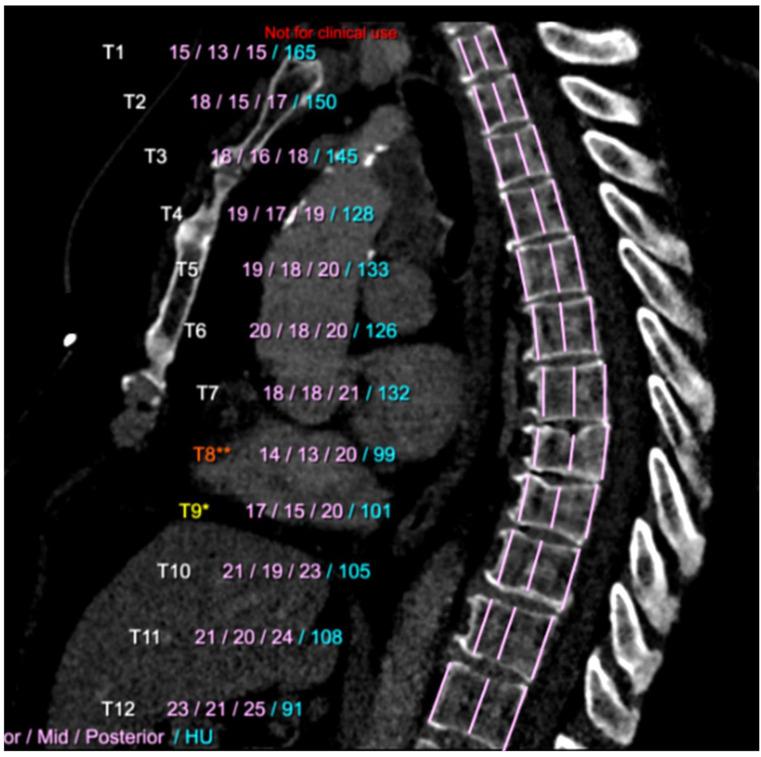

Two large randomized controlled trials of low-dose CT (LDCT)-based lung cancer screening (LCS) in high-risk smoker populations have shown a reduction in the number of lung cancer deaths in the screening group compared to a control group. Even if various countries are currently considering the implementation of LCS programs, recurring doubts and fears persist about the potentially high false positive rates, cost-effectiveness, and the availability of radiologists for scan interpretation. Artificial intelligence (AI) can potentially increase the efficiency of LCS. The objective of this article is to review the performances of AI algorithms developed for different tasks that make up the interpretation of LCS CT scans, and to estimate how these AI algorithms may be used as a second reader. Despite the reduction in lung cancer mortality due to LCS with LDCT, many smokers die of comorbid smoking-related diseases. The identification of CT features associated with these comorbidities could increase the value of screening with minimal impact on LCS programs. Because these smoking-related conditions are not systematically assessed in current LCS programs, AI can identify individuals with evidence of previously undiagnosed cardiovascular disease, emphysema or osteoporosis and offer an opportunity for treatment and prevention.

两项针对高危吸烟人群进行的基于低剂量CT(LDCT)的肺癌筛查(LCS)大型随机对照试验表明,与对照组相比,筛查组的肺癌死亡人数有所减少。尽管目前各国都在考虑实施LCS计划,但对于潜在的高假阳性率、成本效益以及放射科医生进行扫描解读的可用性,仍存在反复的疑虑和担忧。人工智能(AI)有可能提高LCS的效率。本文的目的是回顾为构成LCS CT扫描解读的不同任务而开发的AI算法的性能,并估计这些AI算法如何用作第二阅片者。尽管LDCT的LCS降低了肺癌死亡率,但许多吸烟者死于与吸烟相关的合并症。识别与这些合并症相关的CT特征可以在对LCS计划影响最小的情况下提高筛查价值。由于目前的LCS计划中没有系统地评估这些与吸烟相关的情况,AI可以识别出有先前未诊断出的心血管疾病、肺气肿或骨质疏松症证据的个体,并提供治疗和预防的机会。